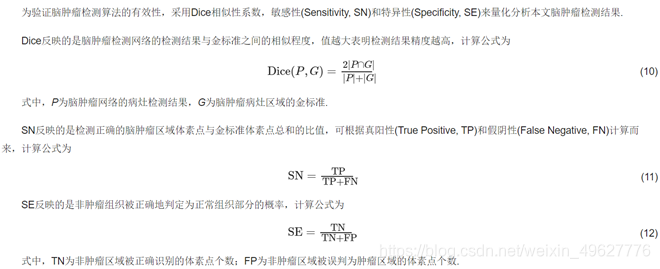

评价标准: